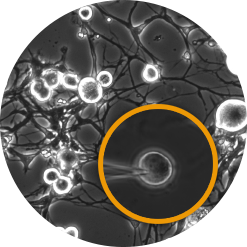

Human iPSC-derived neurons

We are able to physiologically characterise your cells / evaluate your compound’s efficacy on:

• Proprietary iPSCs

• Commercially available iPSCs

Measurements

• Membrane properties

• Voltage-gated ion channels

• Ligand-gated ion channels

• GPCR modulation